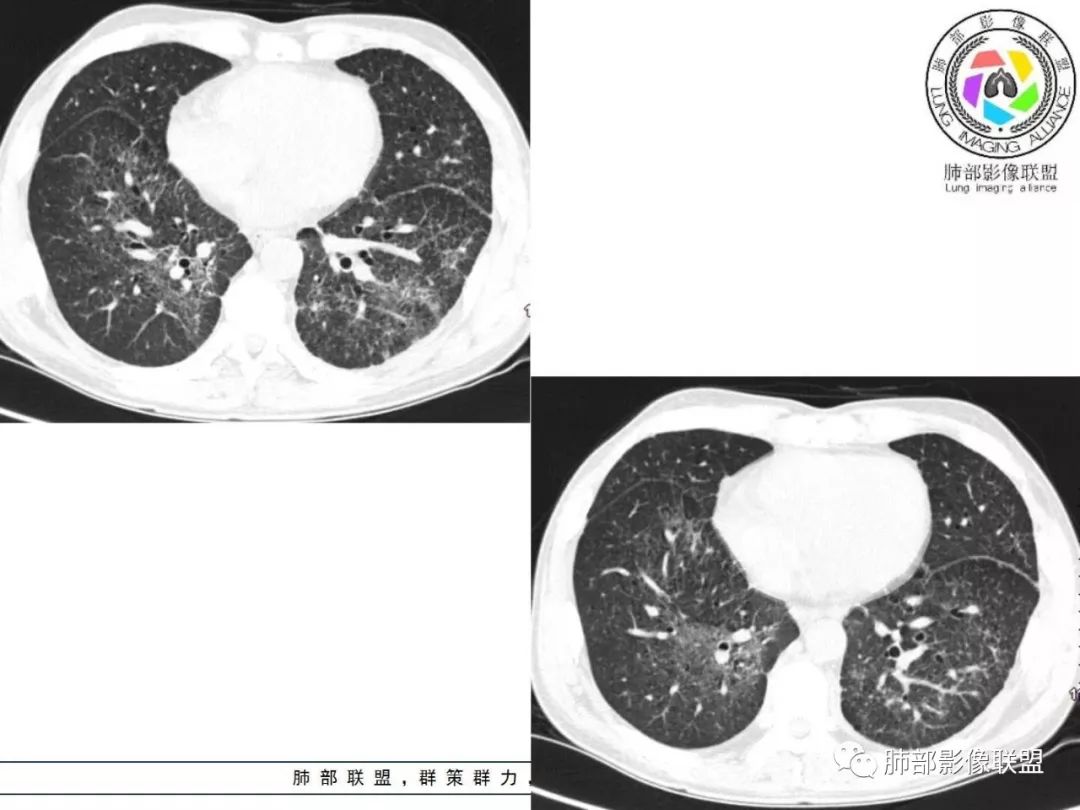

双肺间质性病变,中央间质增厚,胸膜下间质增厚,左侧胸膜肥厚,胸廓变小,肋间隙变窄。

胸部CT:两肺弥漫病灶,磨玻璃影,少许实变,部分累及胸膜,磨玻璃区可见囊?少许胸腔积液,两肺可见结节,支气管血管束增粗,小叶间隔增厚,支气管走形有扭曲扩张,可见纤维化。气肿、大泡。考虑:感染性病变,PCP?查下HIV,CD4,G等。鉴别结核、结缔组织病肺浸润。

55多男性,发热为主诉,体温38℃-39℃多,午后及夜间发热为主,峰值40℃,伴黄痰,CRP高,血糖正常,胸部CT:两肺弥漫病灶,磨玻璃影,少许实变,部分累及胸膜,两肺可见结节,似可见树芽,支气管血管束增粗,小叶间隔增厚,见肺气肿、大泡。考虑感染性病娈,肺结核可能性大。

患者中年男性,发热1月,体温38℃-39℃,峰值40℃,无畏寒、寒战,伴黄痰,CRP升高明显,降钙素原稍升高,血沉、血糖正常。胸部CT:两肺弥漫病变,磨玻璃影+点片渗出,部分累及胸膜,磨玻璃区边界清楚,少许胸腔积液,两肺支气管血管束增粗,小叶间隔增厚,部分支气管走形有扭曲扩张,可见肺气肿、右肺尖肺大泡及部分纤维化改变。综合考虑:感染性病变。结核或PCP可能性大,鉴别风湿免疫、结缔组织疾病肺浸润和腺癌等恶性病变。

胸部CT:两肺弥漫病灶,中央间质分布为主,部分位于胸膜及叶间裂旁,磨玻璃影,斑片影,部分实性结节,肺气囊,支气管血管束增粗,小叶间隔增厚,叶间裂不均匀增厚,支气管走形有扭曲扩张,可见纤维化、气肿、大泡。考虑:LIP加MALT。鉴别PLCH、PCP、结核、结缔组织病肺浸润。

双肺弥漫性病变,多发磨玻璃密度及小叶间隔增厚,大部分沿支气管血管束分布,伴支气管轻度扩张,以午后及晚上发热为主,考虑感染性病变,间质性结核可能大,另双肺多发肺气囊,LIP待排

中老年男性,双肺弥漫性病变,呈网状、斑片及大片状,实变影及磨玻璃影相间,部分病灶区支气管扩张,并见多发小囊状或蜂窝状透亮影,中央间质增厚,气管前单发小淋巴结。考虑淋巴细胞增生性病变?粘膜相关性淋巴瘤(MALT)或淋巴细胞间质性肺炎(LIP)?鉴别机化性肺炎(OP)及结核(TB)。

间质性肺结核是结核的一种特殊影像学表现,为继发性肺结核,影像学表现与常见的继发性肺结核有所不同,有一定的特征性:

病灶呈片状磨玻璃密度影,呈典型的烟花征。磨玻璃影密度偏高,有网结节样改变,与正常肺实质分界清楚,且常见相对高密度的勾画。

烟花征分为3肿类型:晕征、反晕征及均匀分布。

病变一般沿血管支气管束分布或小叶分布,一般上肺多于下肺(这与常见继发性肺结核分布相若)。

常会伴有其他继发性肺结核病灶,如斑片影、结节影,树芽征,新旧不等改变。

2. 肺气肿背景(小叶中心性肺气肿);双肺多发病灶整体沿血管支气管束及胸膜下分布,以上叶及下叶背段分布为主,有实变及GGO,边界清楚,有树芽,小叶间隔及中央间质增厚,叶间裂见到多发结节,部分支气管不规则牵拉扩张,提示病灶纤维化明显,结合临床病史,考虑病灶为间质性感染,肺门及纵隔内有钙化淋巴结,小叶间隔结节,考虑淋巴道增值性疾病可能,综合常规要怀疑间质性肺结核。